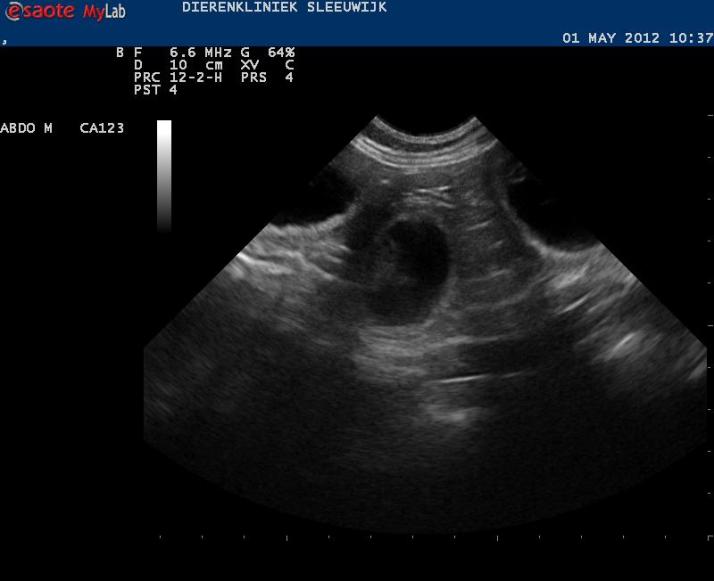

De afspraak voor de echo is gemaakt, ik hoop dat we begin volgende week het eerste bewijs van leven kunnen tonen.

Aan het eind van de week zijn ze 30 mm groot. De hoeveelheid vruchtwater neemt ook toe.